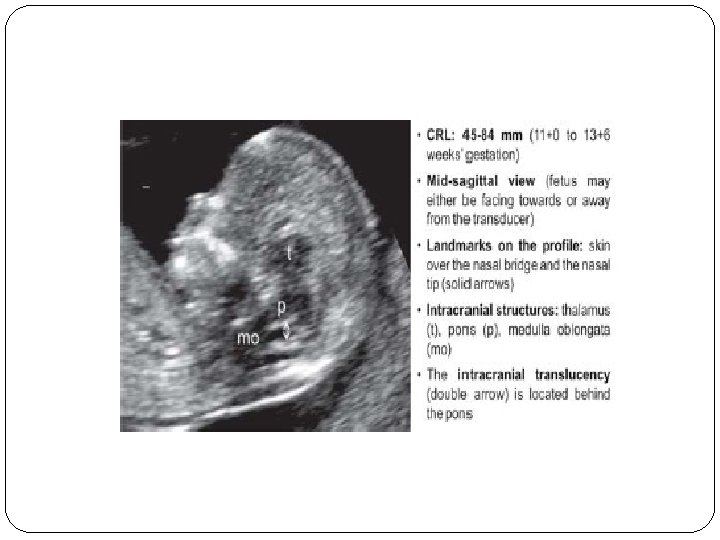

IT(Intracerebral Translucency )

IT…. open NTD �One of the major failings of the first trimester fetal ultrasound examination had been the inability to consistently diagnose open neural tube defects other than the exencephaly/ anencephaly sequence �A recently described intracranial marker [intracerebral translucency (IT)] may overcome this deficiency. � The fetal image required to evaluate the IT is identical to those needed for the NT, NB and FMF angle evaluation

� A magnified midline view of the fetal head and upper thorax is obtained and the following intracranial structures need to be visualized: hypoechoic regions of the thalamus, the pons (brain stem) and the medulla oblongata � The IT represents the fluid filled fourth ventricle, which is located posteriorly to the pons. � The combination of the posterior border of the pons and the floor of the fourth ventricle is seen as a single thin echogenic line, which forms the anterior border of the IT. � The posterior border of the IT is the roof of the fourth ventricle. This is seen also as a relatively thin

� The proposed mechanism for this finding is similar to that of the Chiari type II malformation (banana sign) seen in second trimester fetuses with spina bifida aperta: decreased pressure in the subarachnoid spaces leading to the caudal displacement of the brain. � Measuring the IT does not provide additional information. Therefore, the IT is simply reported as present or absent. � It would be premature to state that the absence or presence of IT has the same predictive value as the intracranial findings in the second trimester. However, the absence of the IT should lead to an extremely careful ultrasound evaluation of the spine at the time of the first trimester ultrasound. If the appearance of the spine is normal on the initial scan, the fetus should be reexamined at approximately 16 weeks. A 20 week scan should also be performed if the 16 week scan is normal.

� So normally, the ratio of the BS to the BSOB will range from 0. 8 at 11 weeks to somewhere around 0. 7 at 14 weeks. In fetuses with open spina bifida, because of the posterior shift of the brain, the BS appears relatively enlarged and shifted backwards, so the BS to BSOB (BS/ BSOB) ratio is increased and it is usually more than one